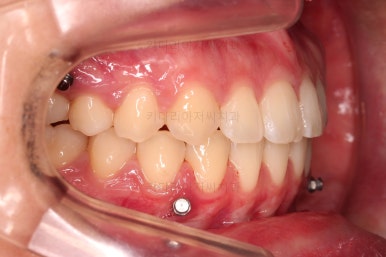

이제 마무리를 해봅니다.

교합 양호하고 치아 사이 틈새도 잘 모아졌습니다.

이제 부산치아교정 전후 비교를 해볼게요.

틈새가 예쁘게 모아졌고요.

교합도 좋아졌고, 앞니도 가지런해졌네요.

이상 미니스크류를 이용해 어금니를 전방으로 당겨오면서 틈새를 모아주었던 부산치아교정 치료사례였습니다.